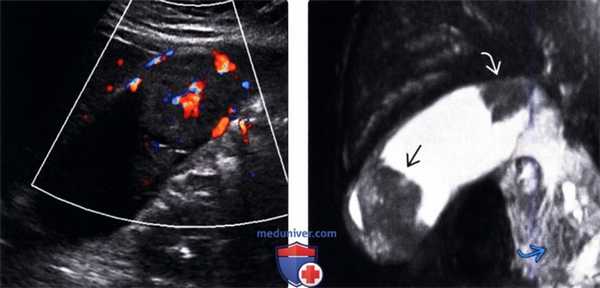

(Левый) У пациентки 67 лет с острым панкреатитом на сагиттальном УЗ срезе определяется крупное полипоидное объемное образование дна желчного пузыря, имеющее собственную сосудистую сеть.

(Правый) При МРТ в просвете желчного пузыря визуализируется дольчатое полипоидное образование, гетерогенное и гиперинтенсивное по сравнению с прилегающей печенью. Обратите внимание на угловатый конкремент в шейке желчного пузыря и отечность поджелудочной железы, вызванную острым интерстициальным отечным панкреатитом.

• Цветовая допплерография:

о Зоны васкуляризации в толще объемного образования

о Наличие у полипа крупнее 1 см васкуляризованной сердцевины